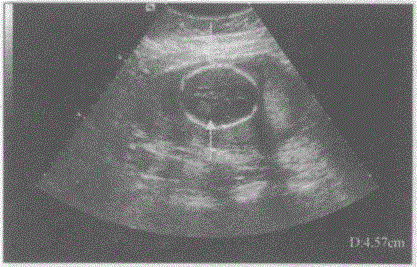

问题 请指出下图箭头所指的是胎儿哪一部位:

选项 A.股骨长径 B.胎盘厚度 C.羊水深度 D.胎儿双顶径

答案 D